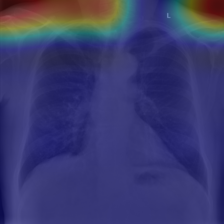

COVID data set. The potential of artificial intelligence and especially deep learning in medicine is huge (EJ., 2019). On the other hand, the medical domain is known to be badly affected by the presence of confounders (Jager et al., 2008; Smith & Nichols, 2018). In order to evaluate the potential of ProtoPDebug to help addressing this issue, we tested it on a challenging real-world problem from the medical imaging domain. The task is to recognize COVID-19 from chest radiographies. As shown in DeGrave et al. (2021), a classifier trained on this dataset heavily relies on confounders that correlate with the presence or absence of COVID. These confounders come from the image acquisition procedure or annotations on the image. We trained and tested ProtoPDebug on the same datasets used in DeGrave et al. (2021) using the data pipeline source code (cod, 2021a). To simplify the identification of confounders, we focused on a binary classification task, discriminating COVID-positive images from images without any pathology. Given the extremely high inter-annotator agreement of the CUB5nat experiment, this experiment was conducted internally in our lab. We leave a crowdsourced evaluation to an extended version of this work.

Results. Fig. 5 reports the (non-zero activation) prototypes of ProtoPDebug at different correction rounds. As for Fig. 4 (left), the left-most column corresponds to the prototypes learned by ProtoPNets. Note that for each prototype, the supervision is given to the 10 most-activated images (). Penalized confounders have been extracted from images on which the prototype has non-zero activation, because they influence the classification. However, the patches of the images to remember are extracted even if the activation is zero, in order to force the prototype to increase the activation on them thanks to the remembering loss. Eventually, ProtoPDebug manages to learn non-confounded prototypes, resulting in substantially improved test classification performance. The test goes from 0.26 of ProtoPNets (first column) to 0.54 at the end of the debugging process.